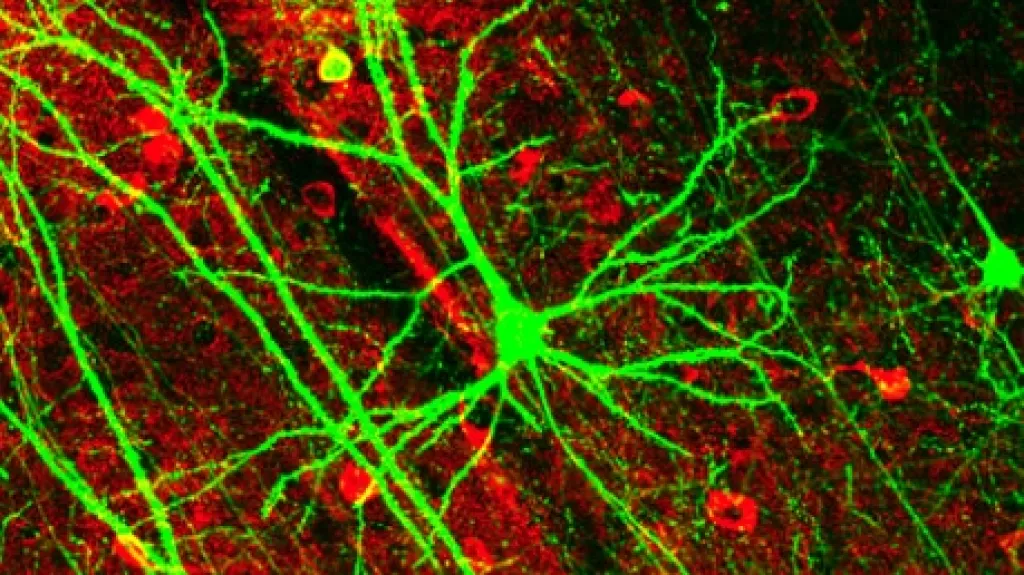

Skupina z univerzity Svatého Raffaela v Miláně použila skenery mozku, aby tímto způsobem prozkoumala jednotlivé mozkové závity a identifikovala proteiny zde uložené. Vědci porovnávali vzorek 242 starších lidí, přičemž 72 z nich mělo mírné a 144 žádné problémy s pamětí.

Během 14 měsíců výzkumu diagnostikovali badatelé u 21 pacientů s mírnými nedostatky paměti Alzheimerovu chorobu. Nicméně při mapování mozku magnetickou rezonancí byli porovnáváni lidé, kteří měli shodné potíže s pamětí a dysfunkce mozku byla mnohem vyšší u vzdělanějších pacientů.

Z výsledků lze tedy usuzovat, že mozek intelektuálů se mnohem lépe vyrovnává s nemocí. Pravděpodobně se tak děje vytvořením jakési kognitivní rezervy, jež tlumí následky Alzheimera.